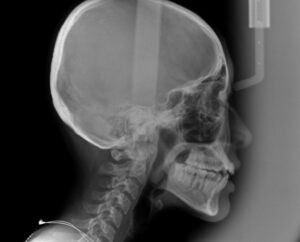

受け口の度合いを調べる

セファロというレントゲン撮影

それから歯科医が治療計画を立てる